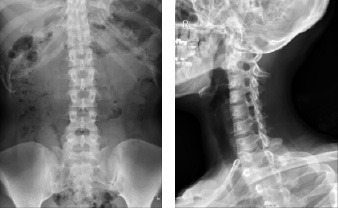

一般撮影の撮影画像

骨の画像

胸の画像